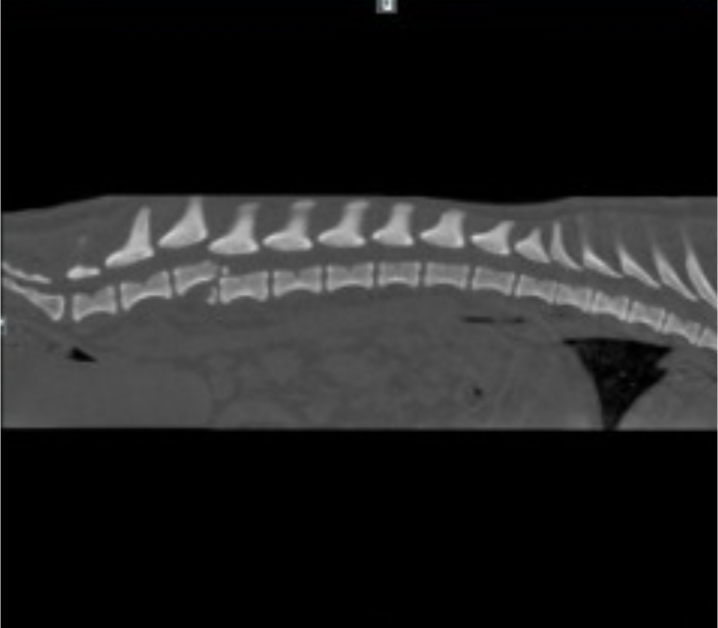

Kochany, radosny piesek.. Taka była Nora. Dwa tygodnie temu.,zrobiła o krok za daleko, w kilka sekund uciekła przez uchyloną przez listonosza furtkę. To naprawdę były sekundy. Moją małą kruszynke potracił samochód. Nora ma uszkodzony rdzeń kregowy, zmiany na nerkach,słaba widoczność pęcherza moczowego, stan zapalny w organizmie. Stan Nory był bardzo zły ale nie pozwoliliśmy jej uśpić .Ten piesek na to nie zasłużył!! Proszę pomóżcie uratować mojego pieska ,który jest dla mnie wszystkim!!!! Moja kochana perełka przeżyła bardzo skomplikowaną operację. Od przyszłego tygodnia zaczynamy rehablitacje Nory. Będziemy jeździć 3 razy w tygodniu na zabiegi i do Pani doktor. Pani doktor powiedziała że zrobiła wszystko co w jej mocy ,ustabilizowała nozki. Nora ma uszkodzony rdzeń kregowy. Pani doktor wysunęła 4 kręg w górę (żeby była ruchomośc)I nałożyła na 5 cement . Nora nie ma czucia w nóżkach, ale będziemy uczyć ja tzw,,chodu rdzeniowego". Nora podnosi głowę do góry,siada,widzi,słyszy,reaguje na imię. W przyszłym tygodniu zaczynamy rehablitacje,czym wcześniej zaczniemy tym lepiej . Na rehablitacje będziemy jeździć 3 razy w tygodniu do kliniki doktora Grzegorza Wąsiatycza w Poznaniu .Za dwa tygodnie,jak Nora nie będzie miała już szwów, to zaczniemy działać na bieżni mokrej . Czy Nora będzie chodzić? Zadaje codziennie ,po kilkanaście razy to pytanie lekarzowi ,chirurgowi, technikowi..odpowiedz zawsze jest ta sama . Czas pokaże... Wszystko zależy od organizmu, od tego jak będziemy ja rehablitować. Ja wierzę... Oczywiście że tak. Błagam o pomoc w uzbieraniu pieniążków na rehabilitację, pomóżcie mojej perełce uzbierać chociaż na jedną wizytę rehabitacyjna.